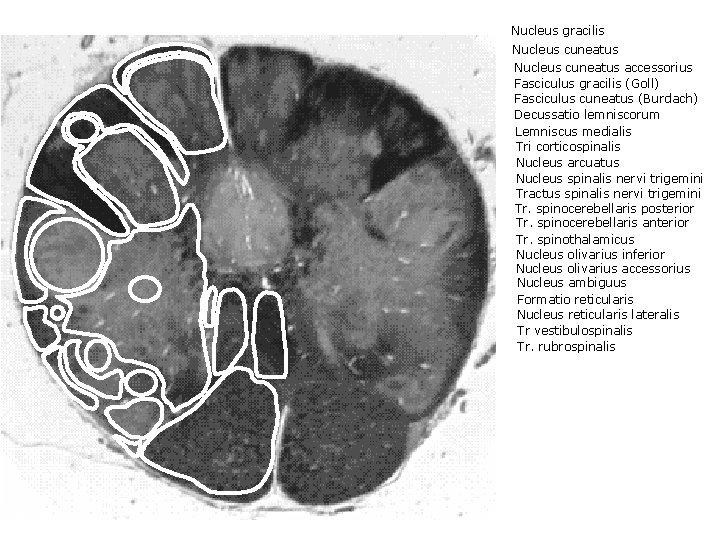

Nucleus gracilis Nucleus cuneatus accessorius Fasciculus gracilis (Goll) Fasciculus cuneatus (Burdach) Decussatio lemniscorum Lemniscus medialis Tri corticospinalis Nucleus arcuatus Nucleus spinalis nervi trigemini Tractus spinalis nervi trigemini Tr. spinocerebellaris posterior Tr. spinocerebellaris anterior Tr. spinothalamicus Nucleus olivarius inferior Nucleus olivarius accessorius Nucleus ambiguus Formatio reticularis Nucleus reticularis lateralis Tr vestibulospinalis Tr. rubrospinalis